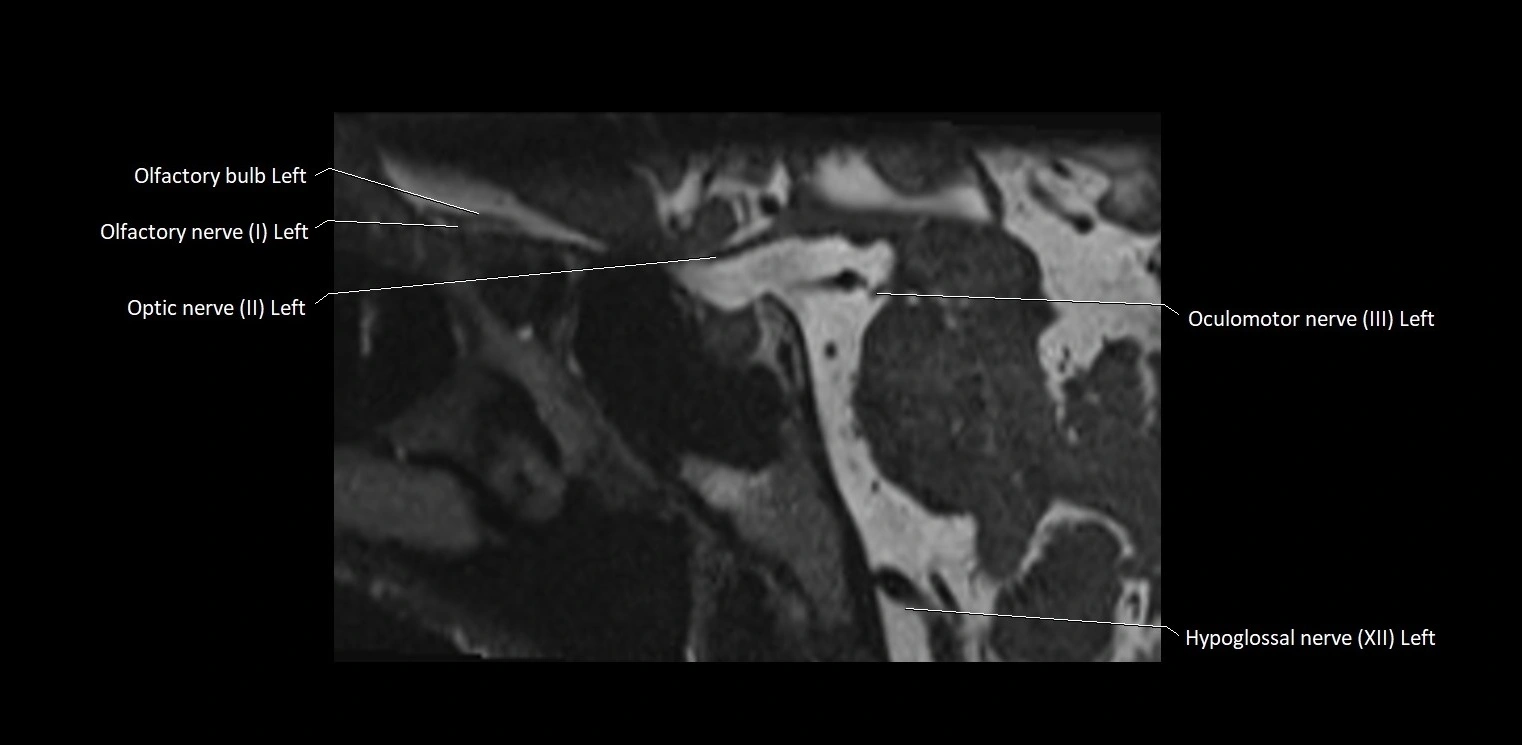

MRI Appearance

• The abducens nerve is a small, thin, linear structure

• Best visualized on high-resolution T2-weighted 3D MRI sequences (e.g., FIESTA or CISS)

• Seen as a hypointense (dark) line running from the brainstem at the pontomedullary junction, traversing the prepontine cistern, and entering Dorello’s canal under the petrosphenoidal ligament, then into the cavernous sinus, and finally the orbit

• May be challenging to visualize in standard MRI due to its small size

• Pathology may be inferred by absence, displacement, or enhancement of the nerve

MRI images

image